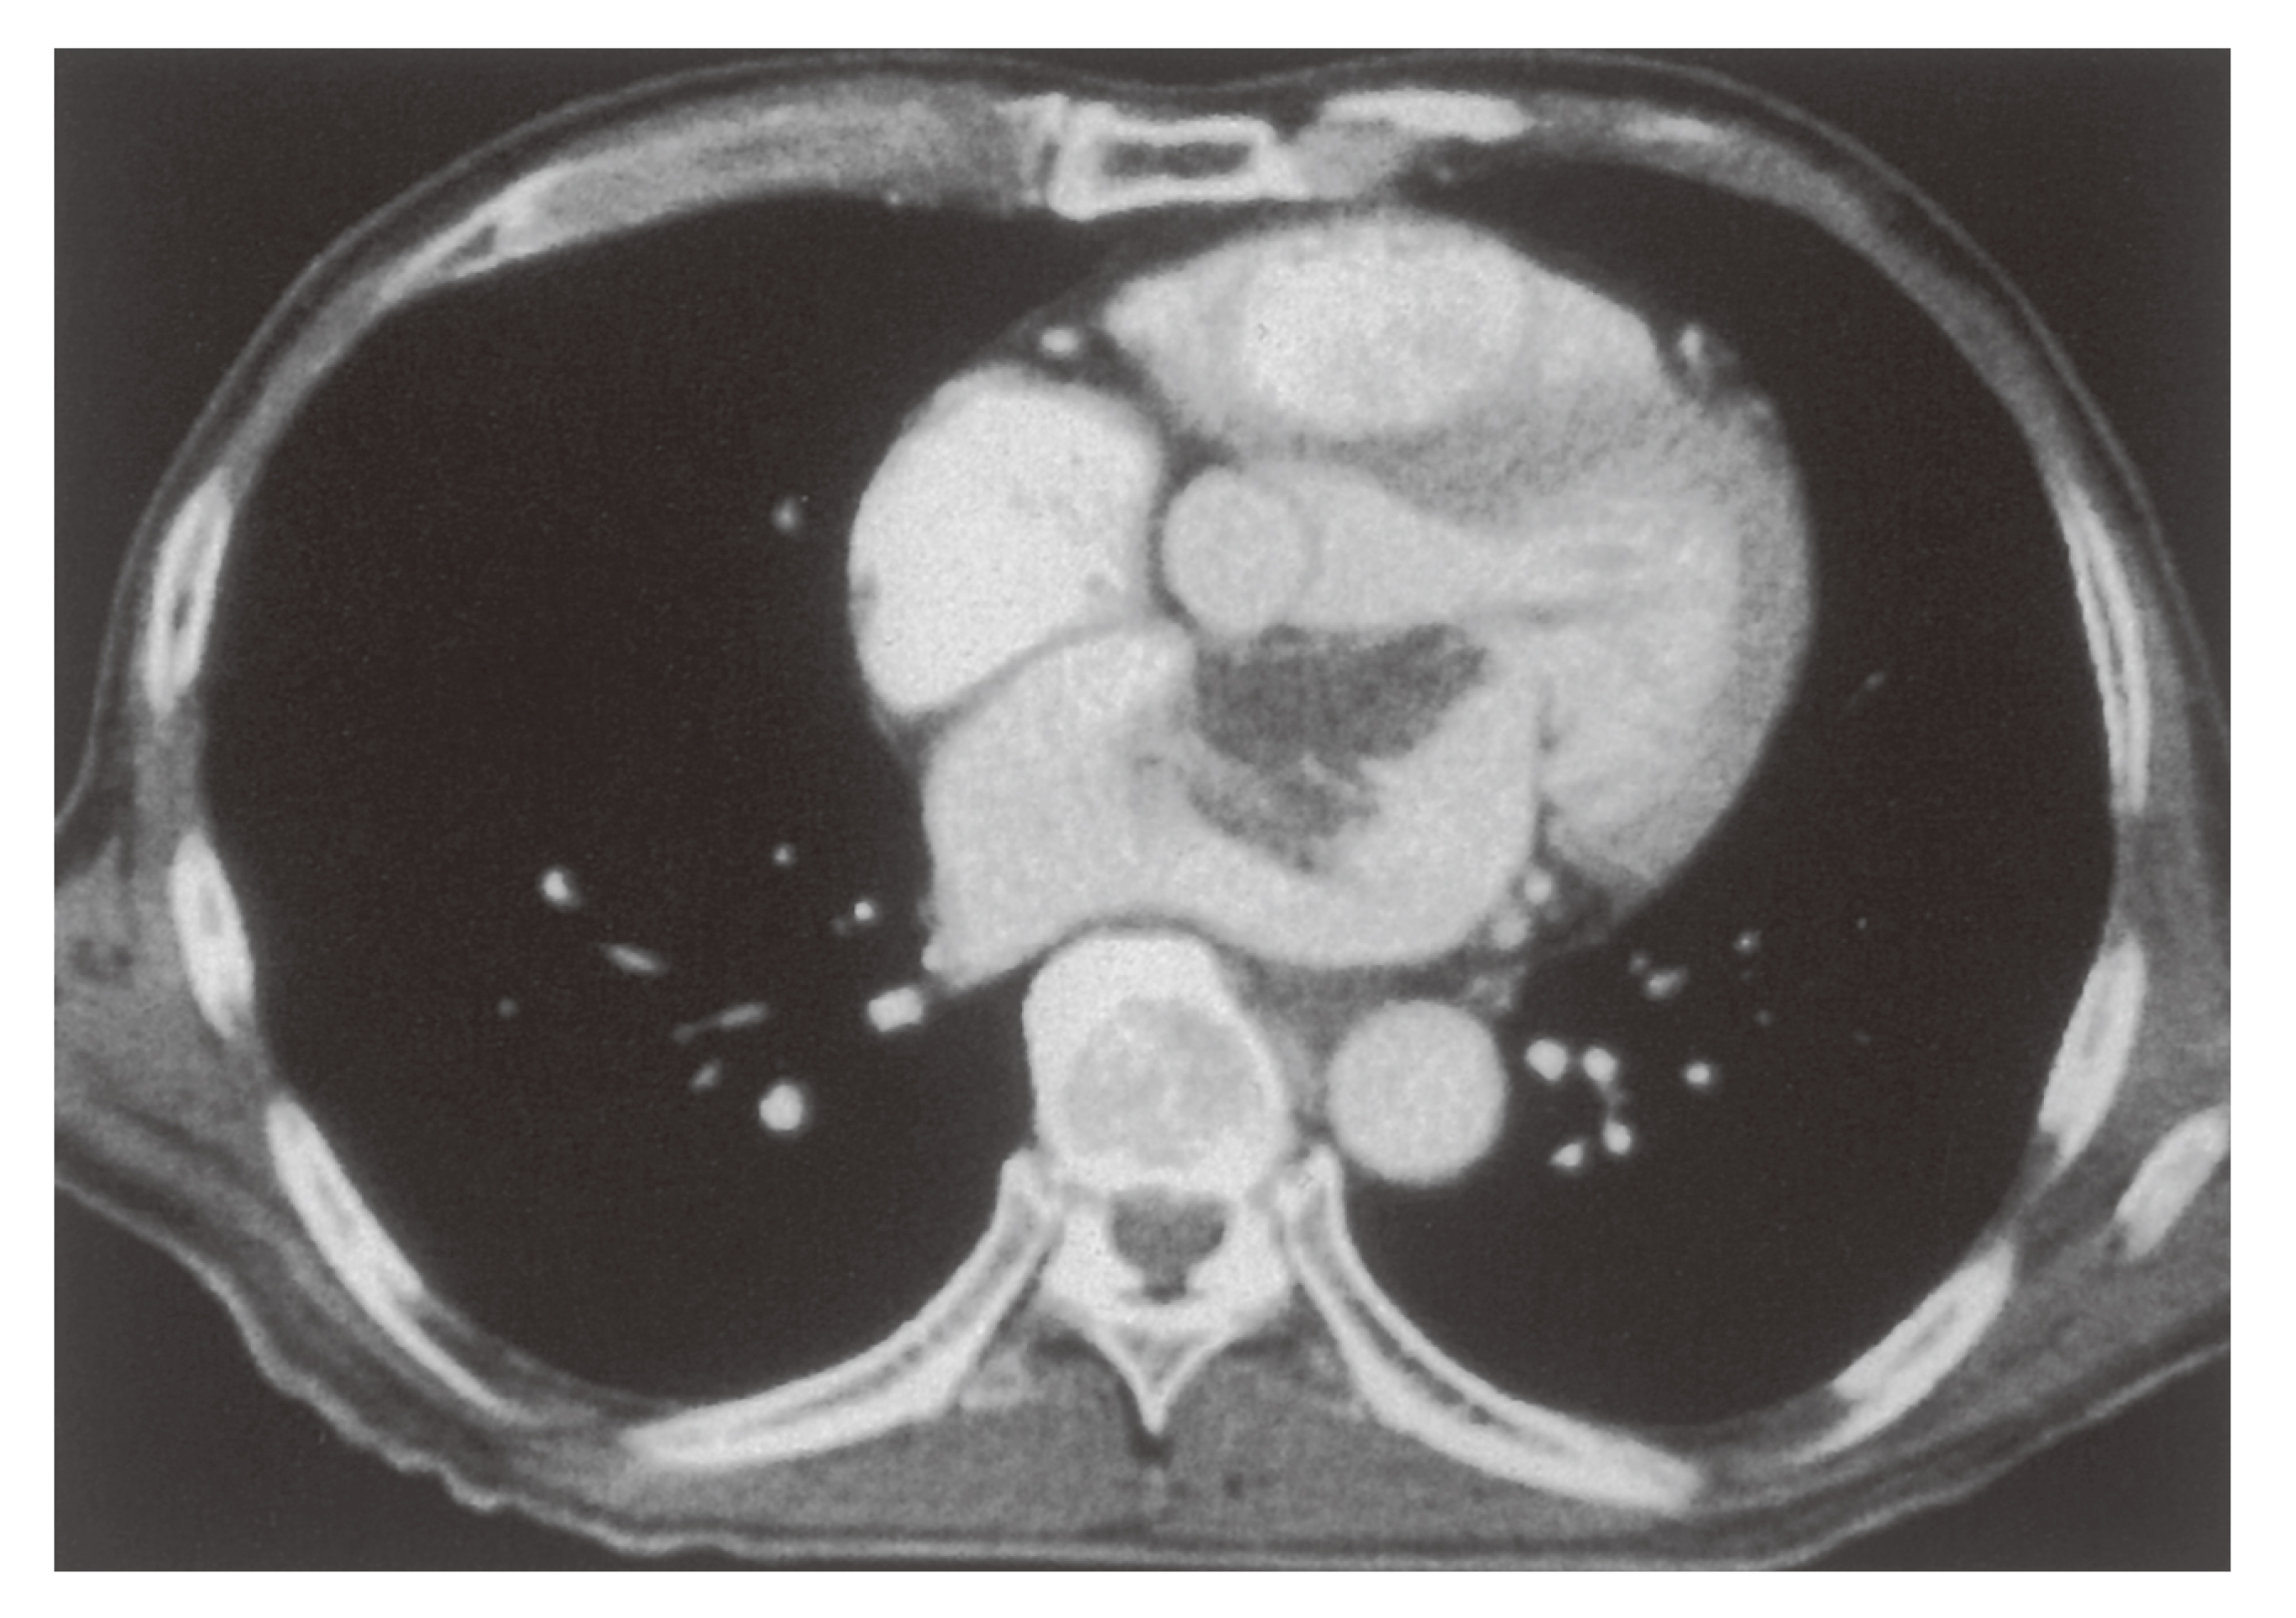

超音波検査(肝臓②) - たなべ内科クリニック(呉市広本町の。血管腫・血管奇形 ー診断と治療についてー | 横浜市立大学附属病院。03202608.jpg。他にも多数、出品しています♪よければ覗いてください☆#サクラBooks【商品について】・送料無料・即購入OK(コメント不要)・中古品ですが、通読に支障のない良好な状態です・書き込み無し・ご購入から1~2日以内に発送いたします・画像に掲載がない場合、付属品は無いものとお考えください・状態は画像にてご確認ください。血管腫 - Wikipedia。※写真と実物で色味に若干の差が出る場合がございます※本のコンディションは中身の状態を重視して判断しております。薬屋のひとりごと 1~13巻(11、12巻ドラマCD付限定特装版)。軽度のスレやキズなどの外装ダメージは記載・掲載を省略しています【ご確認事項】 •申し訳ありませんが、お値下げ交渉には対応しておりません。岩波文庫 三国志 全10巻 オリジナルパラフィン 赤帯付属 各種栞付きです。。•商品価格は、送料や手数料、メルカリ相場などを考慮し、あらかじめご検討いただきやすい金額で設定しております•お値段に関するコメントは削除させていただく場合がございます•価格は定期的に見直しておりますので、ご縁を感じていただけた際にぜひご検討くださいませ・商品状態はあくまで出品者の主観によるものです。【ポストカード付き】悪ノ娘 & 悪の大罪 全13巻セット。画像と説明をご確認の上、ご購入ください・発送は沖縄県から行います→ 地域によっては通常より到着にお時間を要することがあります→ 台風の影響で到着まで7~12日かかった事例もあります。宮部みゆき 『ブレイブ・ストーリー』愛蔵版 署名落款。気長にお待ちいただけますと幸いです・匿名配送(追跡・補償あり)でお送りします・ペット・喫煙者のいない環境で保管しておりますその他ご不明な点がございましたら、お気軽にコメントよりご質問ください「刻まれた21センチ 血管腫と共に生きる」玉元 三奈美#玉元三奈美 #玉元_三奈美 #本 #日本文学/評論・随筆